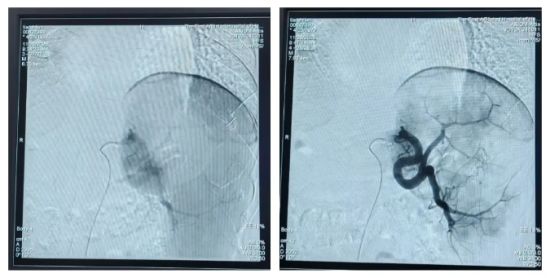

术前脾亢、脾外带广泛显影与术后脾外带2-3cm显影消失的对比